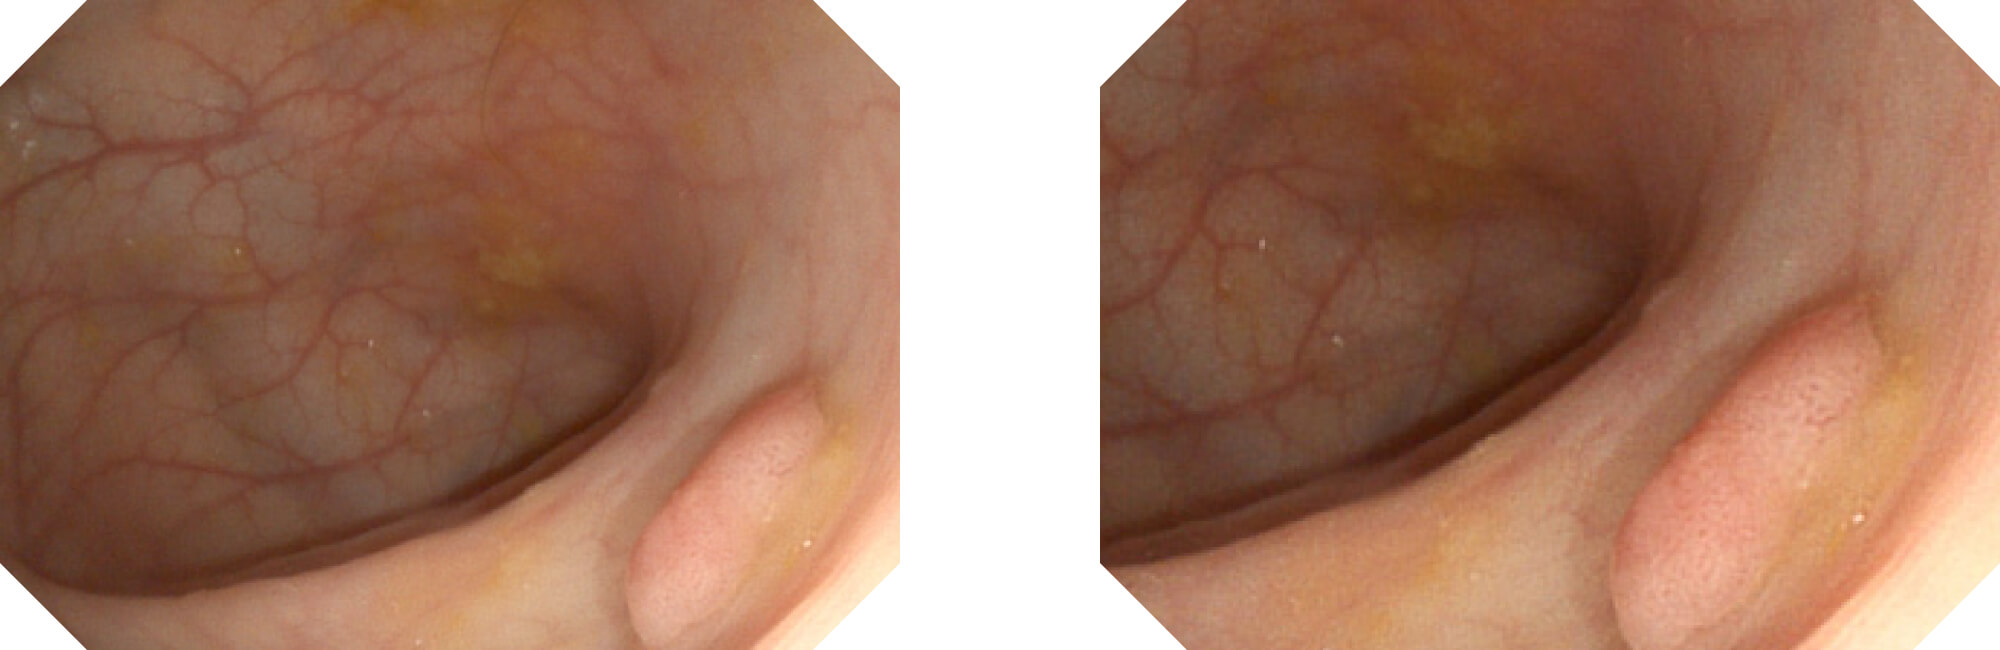

高清数字信号结合构造强调和色彩增强,多重图像处理技术能让每一个图像都清晰可见。

构造强调

色彩增强

利用了血红蛋白在不同波长吸收下系数不同的原理,设计的一种光学域滤波和数字域滤波结合的染色技术,既保证了图像亮度,又可增强黏膜血管的对比度,充分凸显早期病变的细微结构变化,为临床疾病的观察诊断提供更丰富的参考信息。